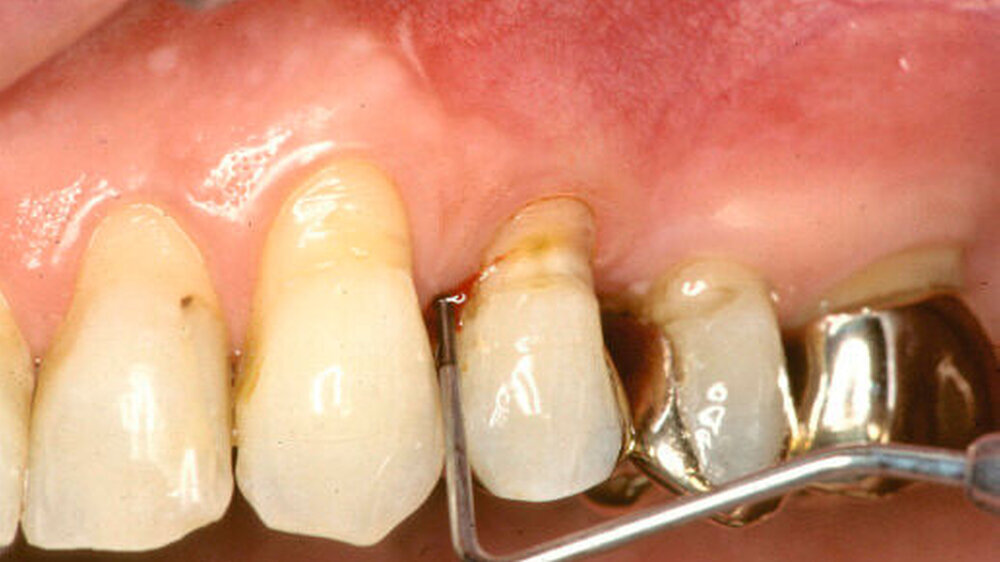

28 gesunde Studenten der Universität Campinas (Brasilien), unter ihnen 14 Nichtraucher und 14 Raucher, nahmen zwischen Juni und September 2012 an der Untersuchung teil. Zu Beginn wurden bei allen Teilnehmern der Plaqueindex, der gingivale Blutungsindex, die Tiefe der Zahnfleischtaschen, epitheliale Haftung und Neigung zur Sondierungsblutung ermittelt.

Abdrücke wurden genommen, um Acrylstents zu präparieren, die einen Bereich von einem unteren mittleren Schneidezahn bis zum zweiten Molaren mit 2 mm des Zahnfleischrandes überdeckten, die beim Zähneputzen getragen werden sollten. Die Probanden erhielten Instruktionen sowie eine Zahnbürste und -pasta für die tägliche Mundpflege. Diese sollte den normalen Gewohnheiten entsprechend durchgeführt werden, allerdings sollte keine Reinigung der Zahnzwischenräume erfolgen sowie kein Mundwasser und kein Kaugummi angewendet werden.

Zu Beginn sowie 14 und 28 Tage nach Induktion der Gingivitis wurden Proben der Zahnbeläge und nach 0, 14, 21 und 28 Tagen Proben von Sulkusflüssigkeit genommen. Aus diesen Proben wurden Daten zur Zusammensetzung der Oralflora gewonnen und Cytokinprofile bestimmt. Zudem wurden eine Woche vor Beginn sowie am Tag 0 und 21 der sichtbare Plaqueindex (VPI) und der gingivale Blutungsindex (GBI) ermittelt.